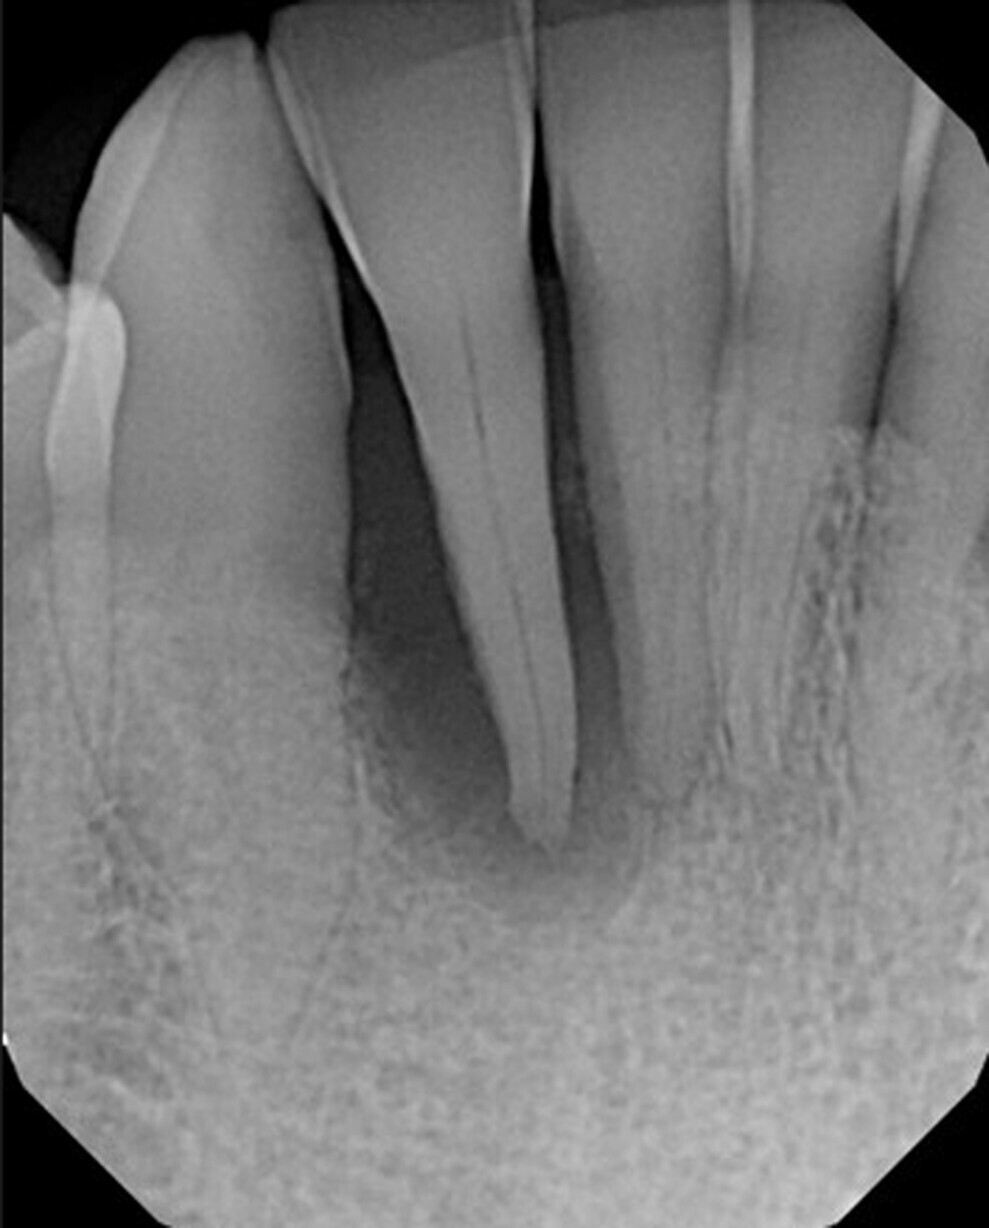

Fig. 1: Periapical radiograph of the maxillary anterior to evaluate the mobile tooth #42 and the adjacent dentition.

A 60-year-old male patient was referred for mobility of the mandibular right lateral incisor (tooth #42) and associated discomfort with the tooth. Examination noted Grade III mobility of tooth #42 and no mobility of the adjacent teeth. A periapical radiograph was taken, and a large lesion was noted around tooth #42, and there was no osseous support (Fig. 1). A thin area of bone was noted between tooth #41 and tooth #42, and we suspected possible involvement of the apical area of tooth #41 regarding the lesion around tooth #42. Tooth #41 had no percussion sensitivity, and the patient did not indicate any temperature sensitivity in the area prior to the appointment.